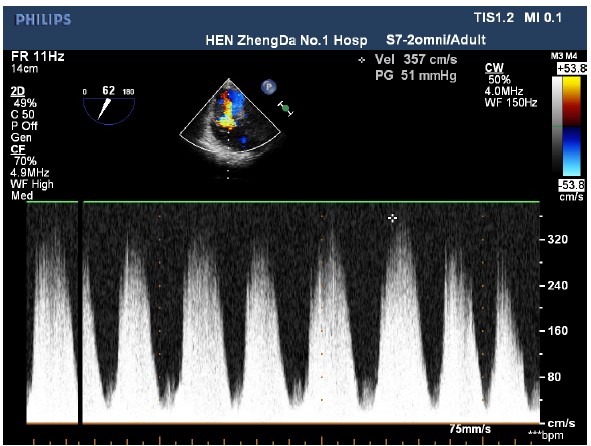

The patient entered the operating room and her ECG was monitored regularly. The induction of anesthesia was smooth. When the surgical team was manipulating the fracture, her blood pressure (BP) suddenly decreased to 63/43 mmHg, heart rate increased to 112 beats/min, and the saturation of pulse oxygen (SpO2) fell to 72%. 1 mg methoxamine was used to raise the blood pressure without success. 2 mg methoxamine, 6 mg ephedrine, and 8 μg nonadrenaline were subsequently given without significant blood pressure change. The central venous pressure was 15mmHg. In addition, the end tidal carbon dioxide decreased to 10 mmHg. There were no significant airway pressure changes. While an allergic reaction was initially suspected, no dermatological changes were identified. Emergency blood gas indicated a partial pressure of artery carbon dioxide (PaCO2) of 77.9 mmHg, and an oxygen partial pressure of 67mmHg. Potential pulmonary embolism was suspected. A transesophageal echocardiography (TEE) was followed. It revealed an enlarged right atrium (Figure1), hypokinesia of the free right ventricle wall, and poor filling of left ventricular. The ratio of left/right ventricular apparent disorder and the pressure of tricuspid valve was 51mmHg with massive regurgitation of 3.57m/s (Figure 2). Severe tricuspid reflux was also observed (Figure 3). Epinephrine and milrinone along with high-dose vasopressin were initiated. While no thrombi in the pulmonary or right ventricle were identified, unstable hemodynamics, changes in carbon dioxide, findings in TEE strongly suggested a possible major PE. Extracorporeal membrane oxygenation (ECMO) was immediately established and an emergent pulmonary thromboembolectomy was successfully performed. The patient was transferred to the surgical intensive care unit for monitoring and evaluation. The patient was discharged without residual deficits after 20 days in surgical intensive care unit.

Figure 3: Tricuspid valve regurgitation on 2D-transesophageal echovardiography. Severe beam of tricuspid valve regurgitation was observed.